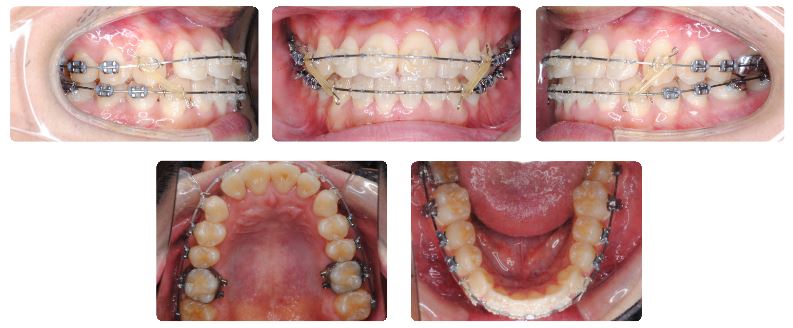

最初の症例は成人男性ですでに前歯の被蓋(前歯の咬み合わせ)はなんとか改善はしておりますが、さらに下顎の側方歯を後方に傾斜させる目的でカリエールモーションを装着することにしました。

下顎用カリエールモーションを装着前の状態です。

上顎前歯が下顎前歯にぶつかり突きあがってしまっている状態です。

このままでは上顎前歯にみられるスペースがなかなか閉じきれないと考えられます。

下顎側方歯にカリエールモーションを装着した直後の状態です。